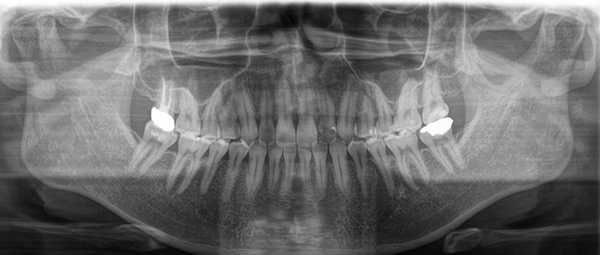

歯周病は顎の骨を溶かしていく病気です。レントゲン撮影を行うことで、顎の骨の状態を確認します。